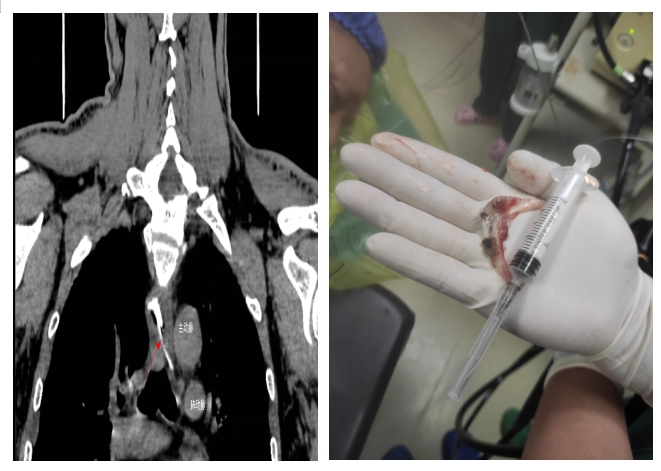

當(dāng)日,黃先生在家中與家人聚餐時(shí),不小心被魚頭骨卡住,強(qiáng)行吞咽多次,出現(xiàn)食管與胸骨中上段后部疼痛,火速到衡陽市中心醫(yī)院就診。接診醫(yī)師對患者進(jìn)行評估,嘗試經(jīng)喉鏡治療時(shí),發(fā)現(xiàn)魚頭骨位置較深,行CT檢查發(fā)現(xiàn)魚頭骨卡于食管中段,穿破食管壁,與主動(dòng)脈比鄰,非常危險(xiǎn),隨時(shí)威脅患者生命安全。隨即,患者被收治到心胸外科住院。入院后,廖金文主任一邊安慰,緩解患者的緊張情緒,一邊為其制定詳細(xì)的治療方案,計(jì)劃在手術(shù)室中嘗試胃鏡下取出魚刺。

在全身麻醉下,通過胃鏡,手術(shù)醫(yī)師清晰可見魚頭骨嵌頓部位為食管中上段。消化內(nèi)科副主任醫(yī)師劉昌智及主管護(hù)師羅雯娟攜手術(shù)室護(hù)理團(tuán)隊(duì),憑借豐富的臨床經(jīng)驗(yàn)與技術(shù),10分鐘內(nèi)為患者實(shí)施了胃鏡取異物治療,成功取出魚頭骨,黃先生轉(zhuǎn)危為安。為防止意外,手術(shù)期間,心胸外科醫(yī)師在手術(shù)室全程守護(hù)。